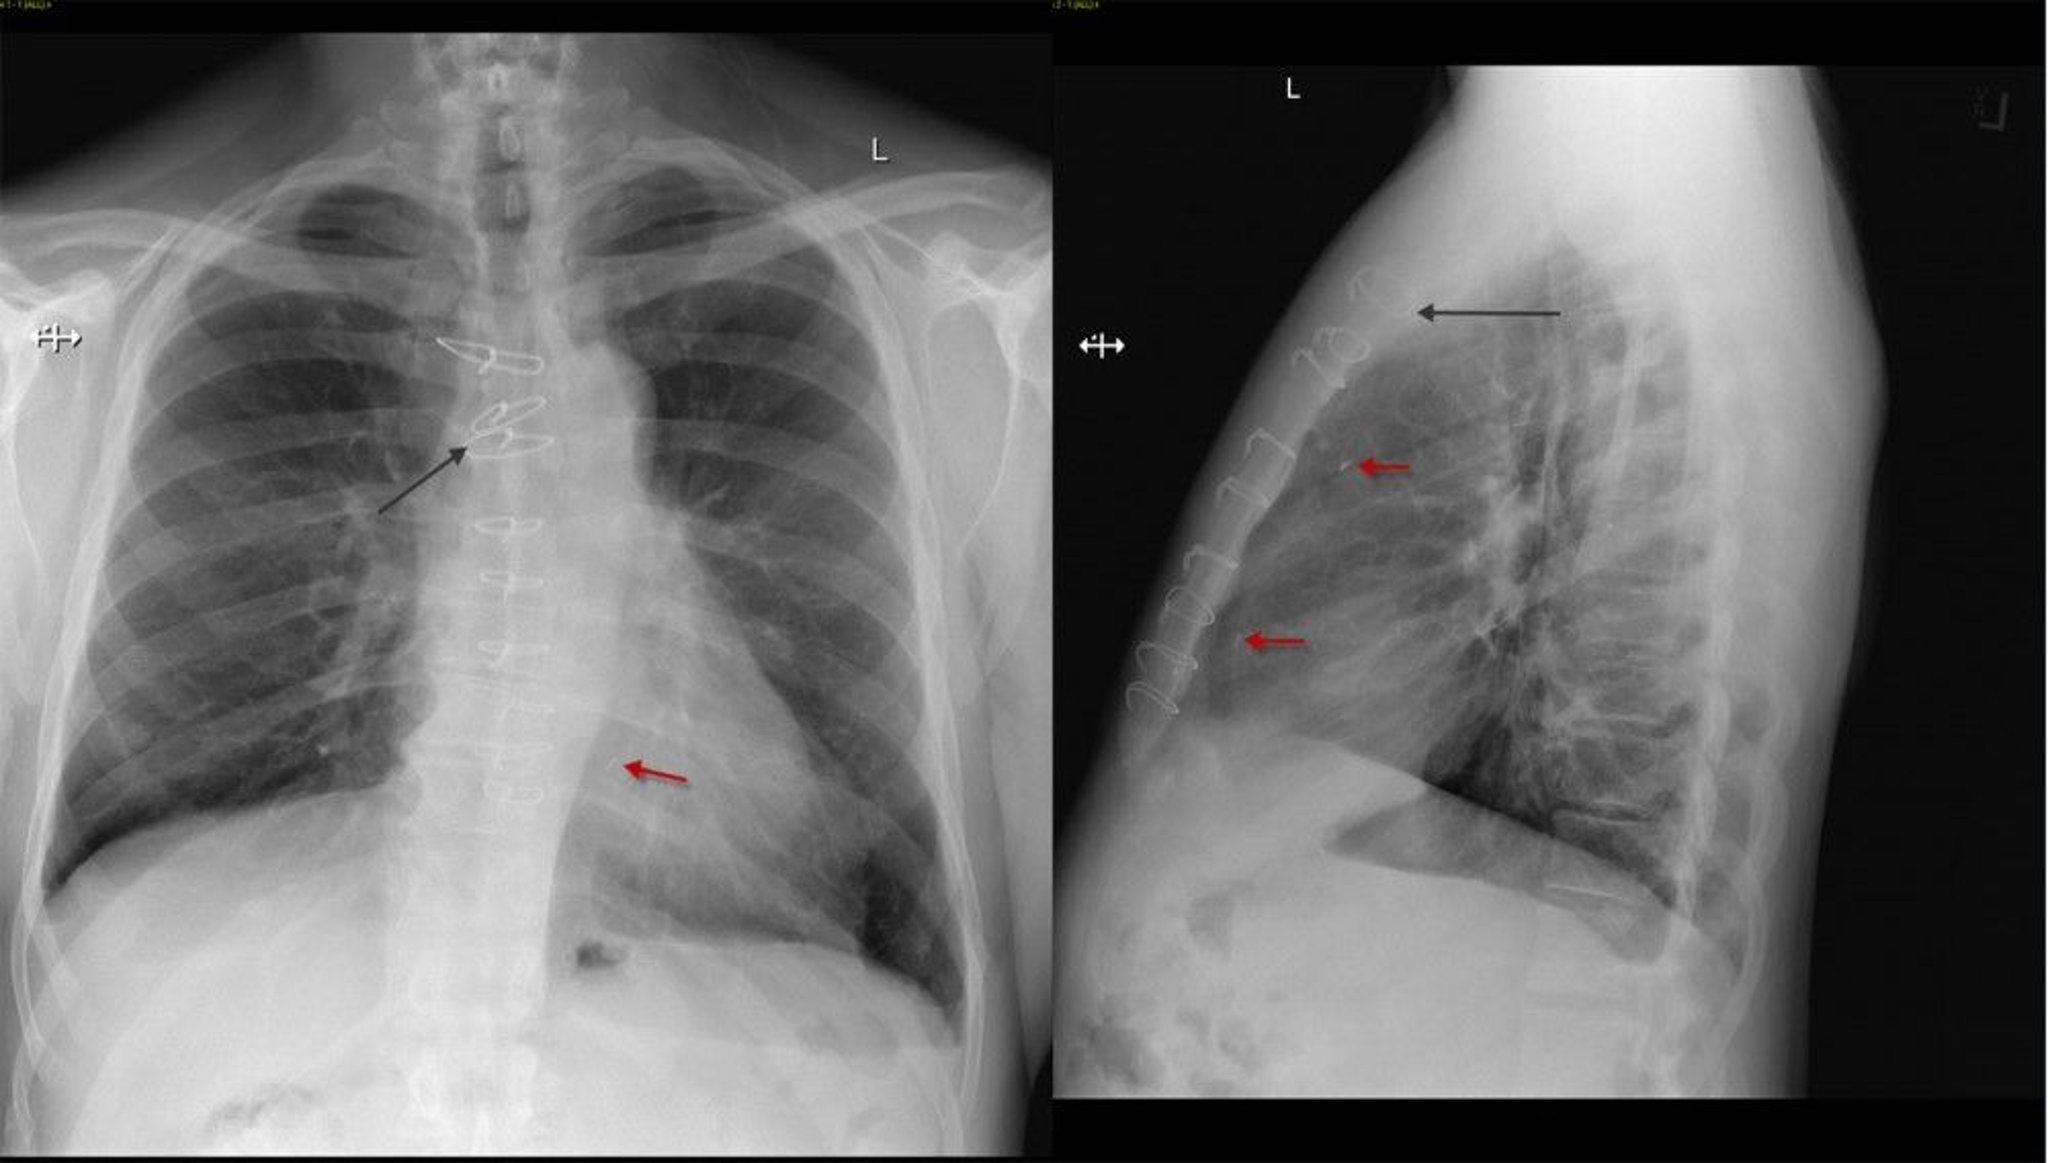

Radiografia de tórax de um paciente após cirurgia de revascularização miocárdica

Radiografia de tórax frontal e lateral de um paciente após cirurgia de revascularização do miocárdio mostrando suturas esternais (seta preta) e clipes cirúrgicos (seta vermelha).